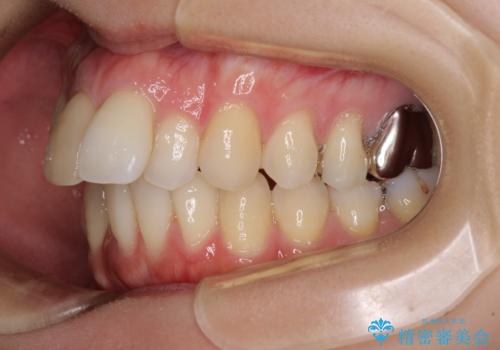

上顎前歯の歯軸が顕著に改善され、非常に口の閉じやすい歯列に仕上げることができました。